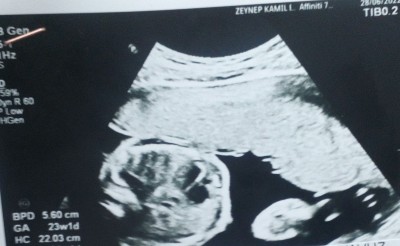

Hanimlar ilk gebeliğim pek anlamıyorum bebek nerde acaba anlayaniniz varmı şimdiden teşekkürler ❤️

Gebelik haftası

23+1

Görüntüde sol tarafta bebeğin karnı sağ tarafta ise ayağı var komple çekemez artık bebeği iyice büyümeye başladı

Yaa bende kafa gibi bişey varya en köşede o sanmıştım

Yok o yuvarlar karnı sağ tarafta nokta nokta olan seyler ayak parmakları

Haftan ileri kuzum o yüzden parça parça çıkıyor ultrason başlığı küçük bebekde büyük o yüzden gözükmüyor ama bu neresi bende anlamadim